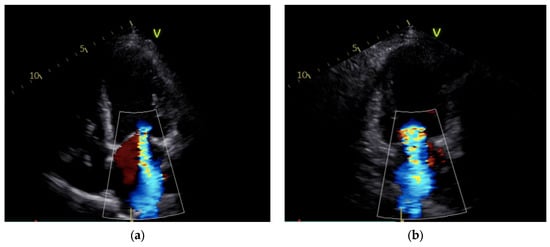

| MR (+) | 2+/3+ | 2+ | 2+ | 3+/4+ (Supplementary Materials Videos S1 and S2) | 2+/3+ | (Supplementary Materials Videos S3–S6) | 1+ (Supplementary Materials Video S7) | 1+ |